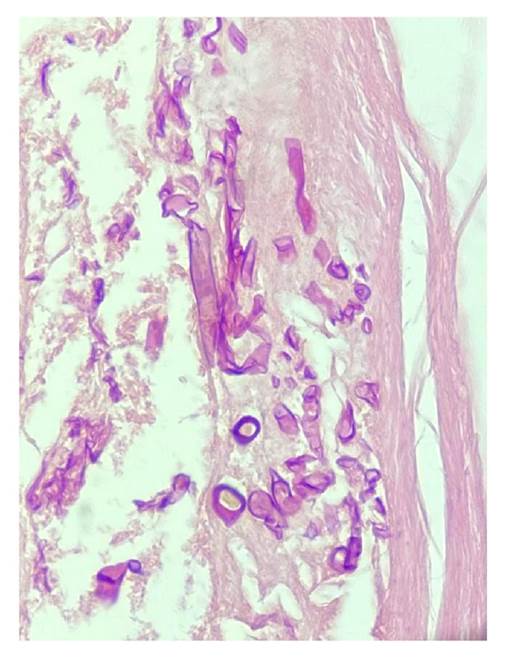

En todos los casos, se identificaron hifas anchas que variaban entre 5 y 20 pm, de contornos irregulares y pleomorfas. Su patrón de ramificación era al azar y, aunque predominaban en ángulo recto, algunas de ellas estaban colapsadas, organizadas en cordones o con doblamiento (figuras 2-5) 1.

Figura 2 Se observa tejido fibroso con una hifa angulada y ramificada con paredes anchas y sincitiales (coenocytic). Hematoxilina y eosina, 40X.

Figura 4 Se observan múltiples estructuras circulares y alargadas de paredes gruesas e irregulares, algunas de ellas sincitiales (coenocytic) e incompletas, sobre un estroma densamente fibroso. Hematoxilina y eosina, 40X.